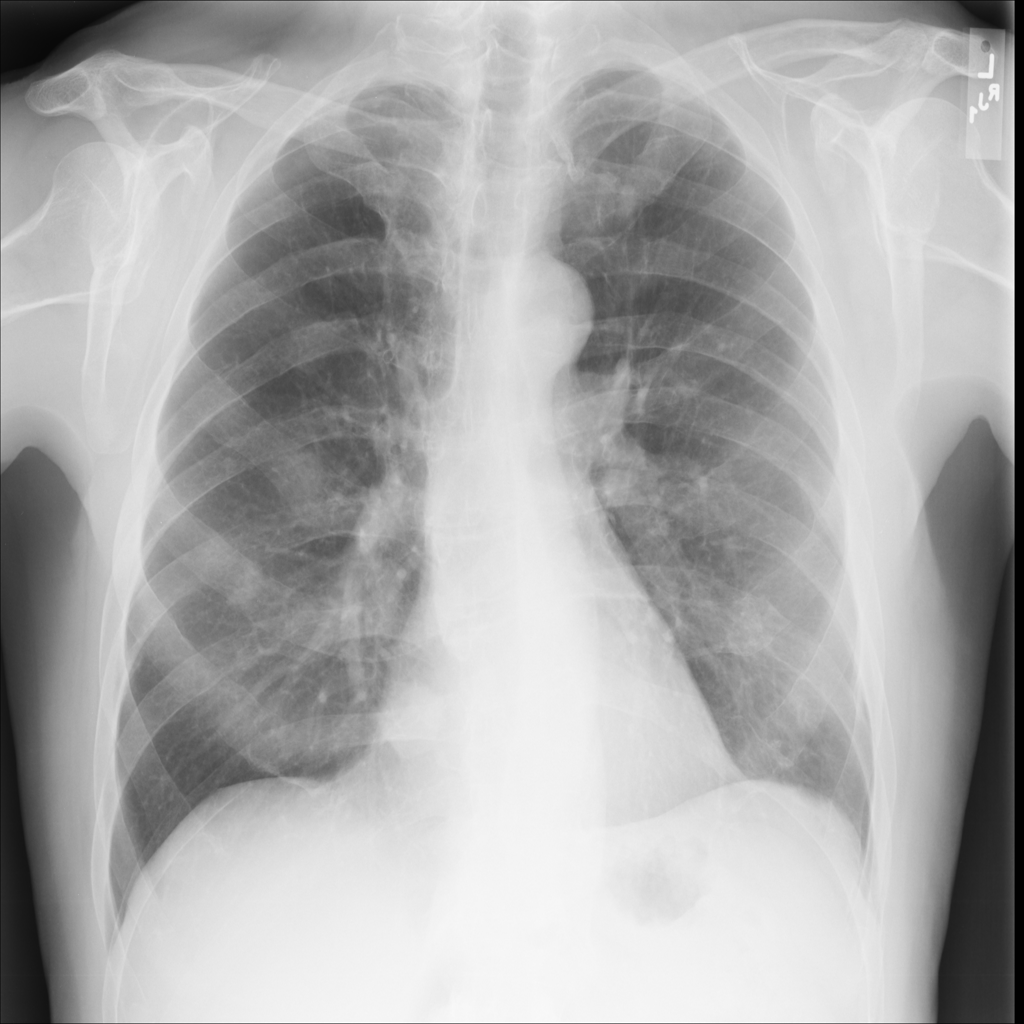

Nodule

A nodule is a small rounded opacity in the lung or chest field. It is a descriptive imaging finding that can be benign or more concerning depending on size, appearance, and context.

Showing up to 90 reference images for Nodule.

PAT-50E5 · IMG-000Nodule

PAT-50E5 · IMG-000

PA